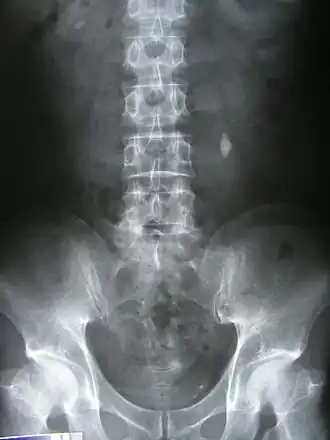

![]() Рентгенограмма, демонстрирующая конкремент в левом мочеточнике | |